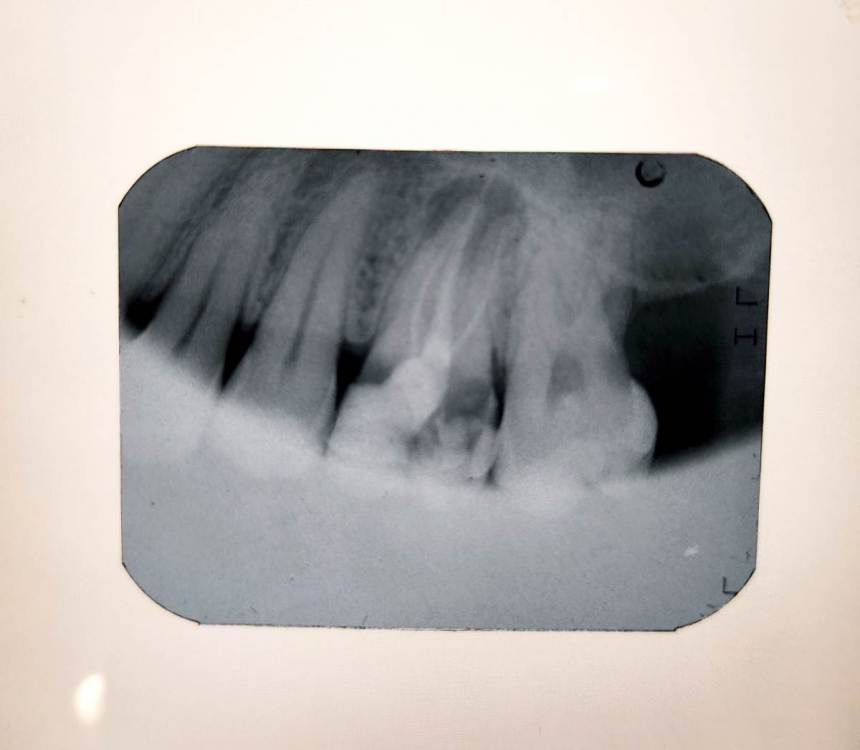

yuliya_glk Опубликовано 30 ноября, 2021 Поделиться Опубликовано 30 ноября, 2021 Здравствуйте, уважаемые специалисты! Необходимо ваше объективное мнение относительно следующей ситуации. Более 8 лет назад была нарощена часть разрушенного 16-го зуба (верхняя правая 6-ка) с удалением нервов и пломбированием каналов. Недавно откололась ещё одна часть этого же зуба (пломба осталась на месте). При обращении за стоматологической помощью был выполнен рентгеновский снимок (прилагается) и КТ. Выявлено воспаление (предположительно киста размером около 9 мм). Затем от разных специалистов получены различные предложения по решению. Один из вариантов включает в себя сохранение зуба, чистку каналов, наложение лекарственного средства и временной пломбы, установкой коронки. Другой предполагает полное удаление зуба и образования с последующим заполнением коллагеном, установкой импланта и коронки. Подскажите, пожалуйста, наиболее целесообразный вариант решения проблемной ситуации. Заранее благодарю! Ссылка на комментарий